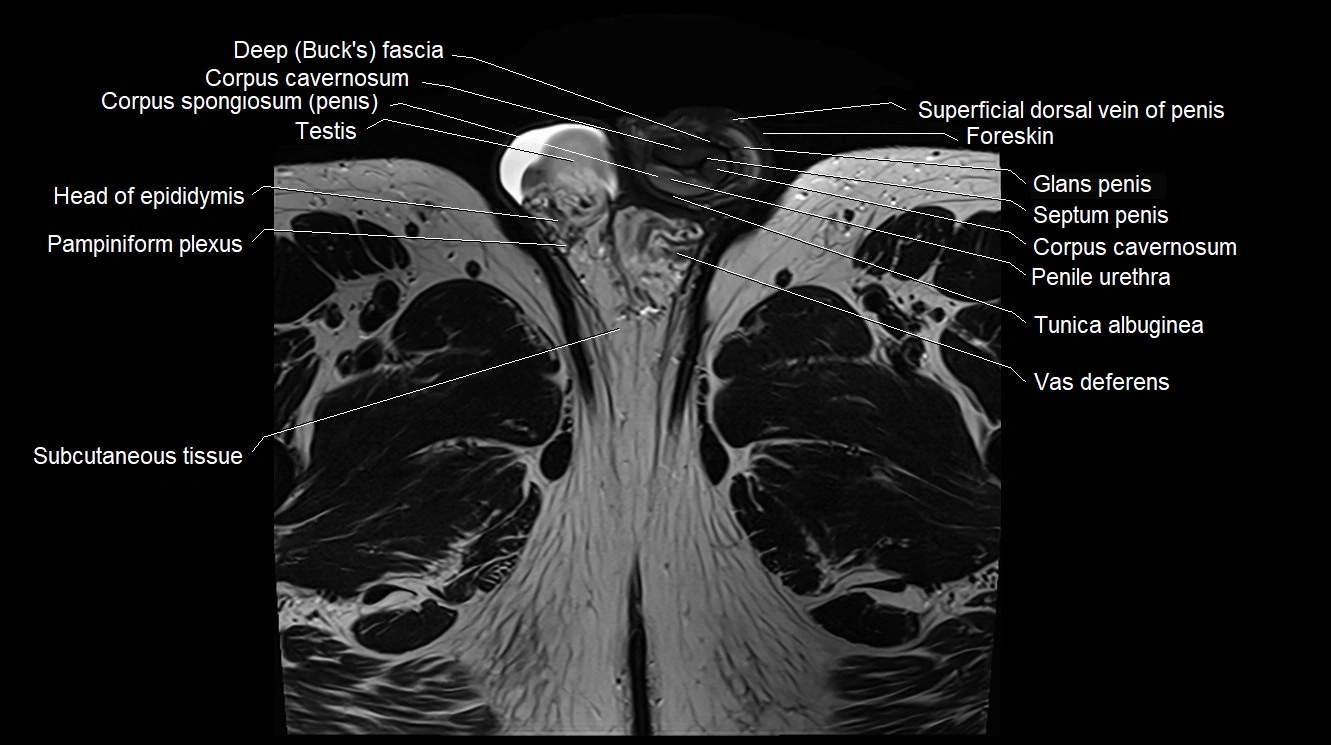

MRI image